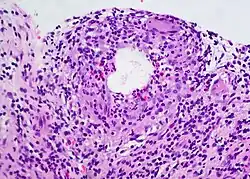

A chalazion (/kəˈleɪziən/; plural chalazia or chalazions) or meibomian cyst[4] is not a cyst but a granuloma[5] in the eyelid that results from a blocked meibomian gland.[6][7] It typically occurs in the middle of the eyelid, red, and not painful.[2] They tend to develop gradually over a few weeks.[2]

Chalazia may recur, and they will usually be biopsied to rule out the possibility of a tumour.[4]